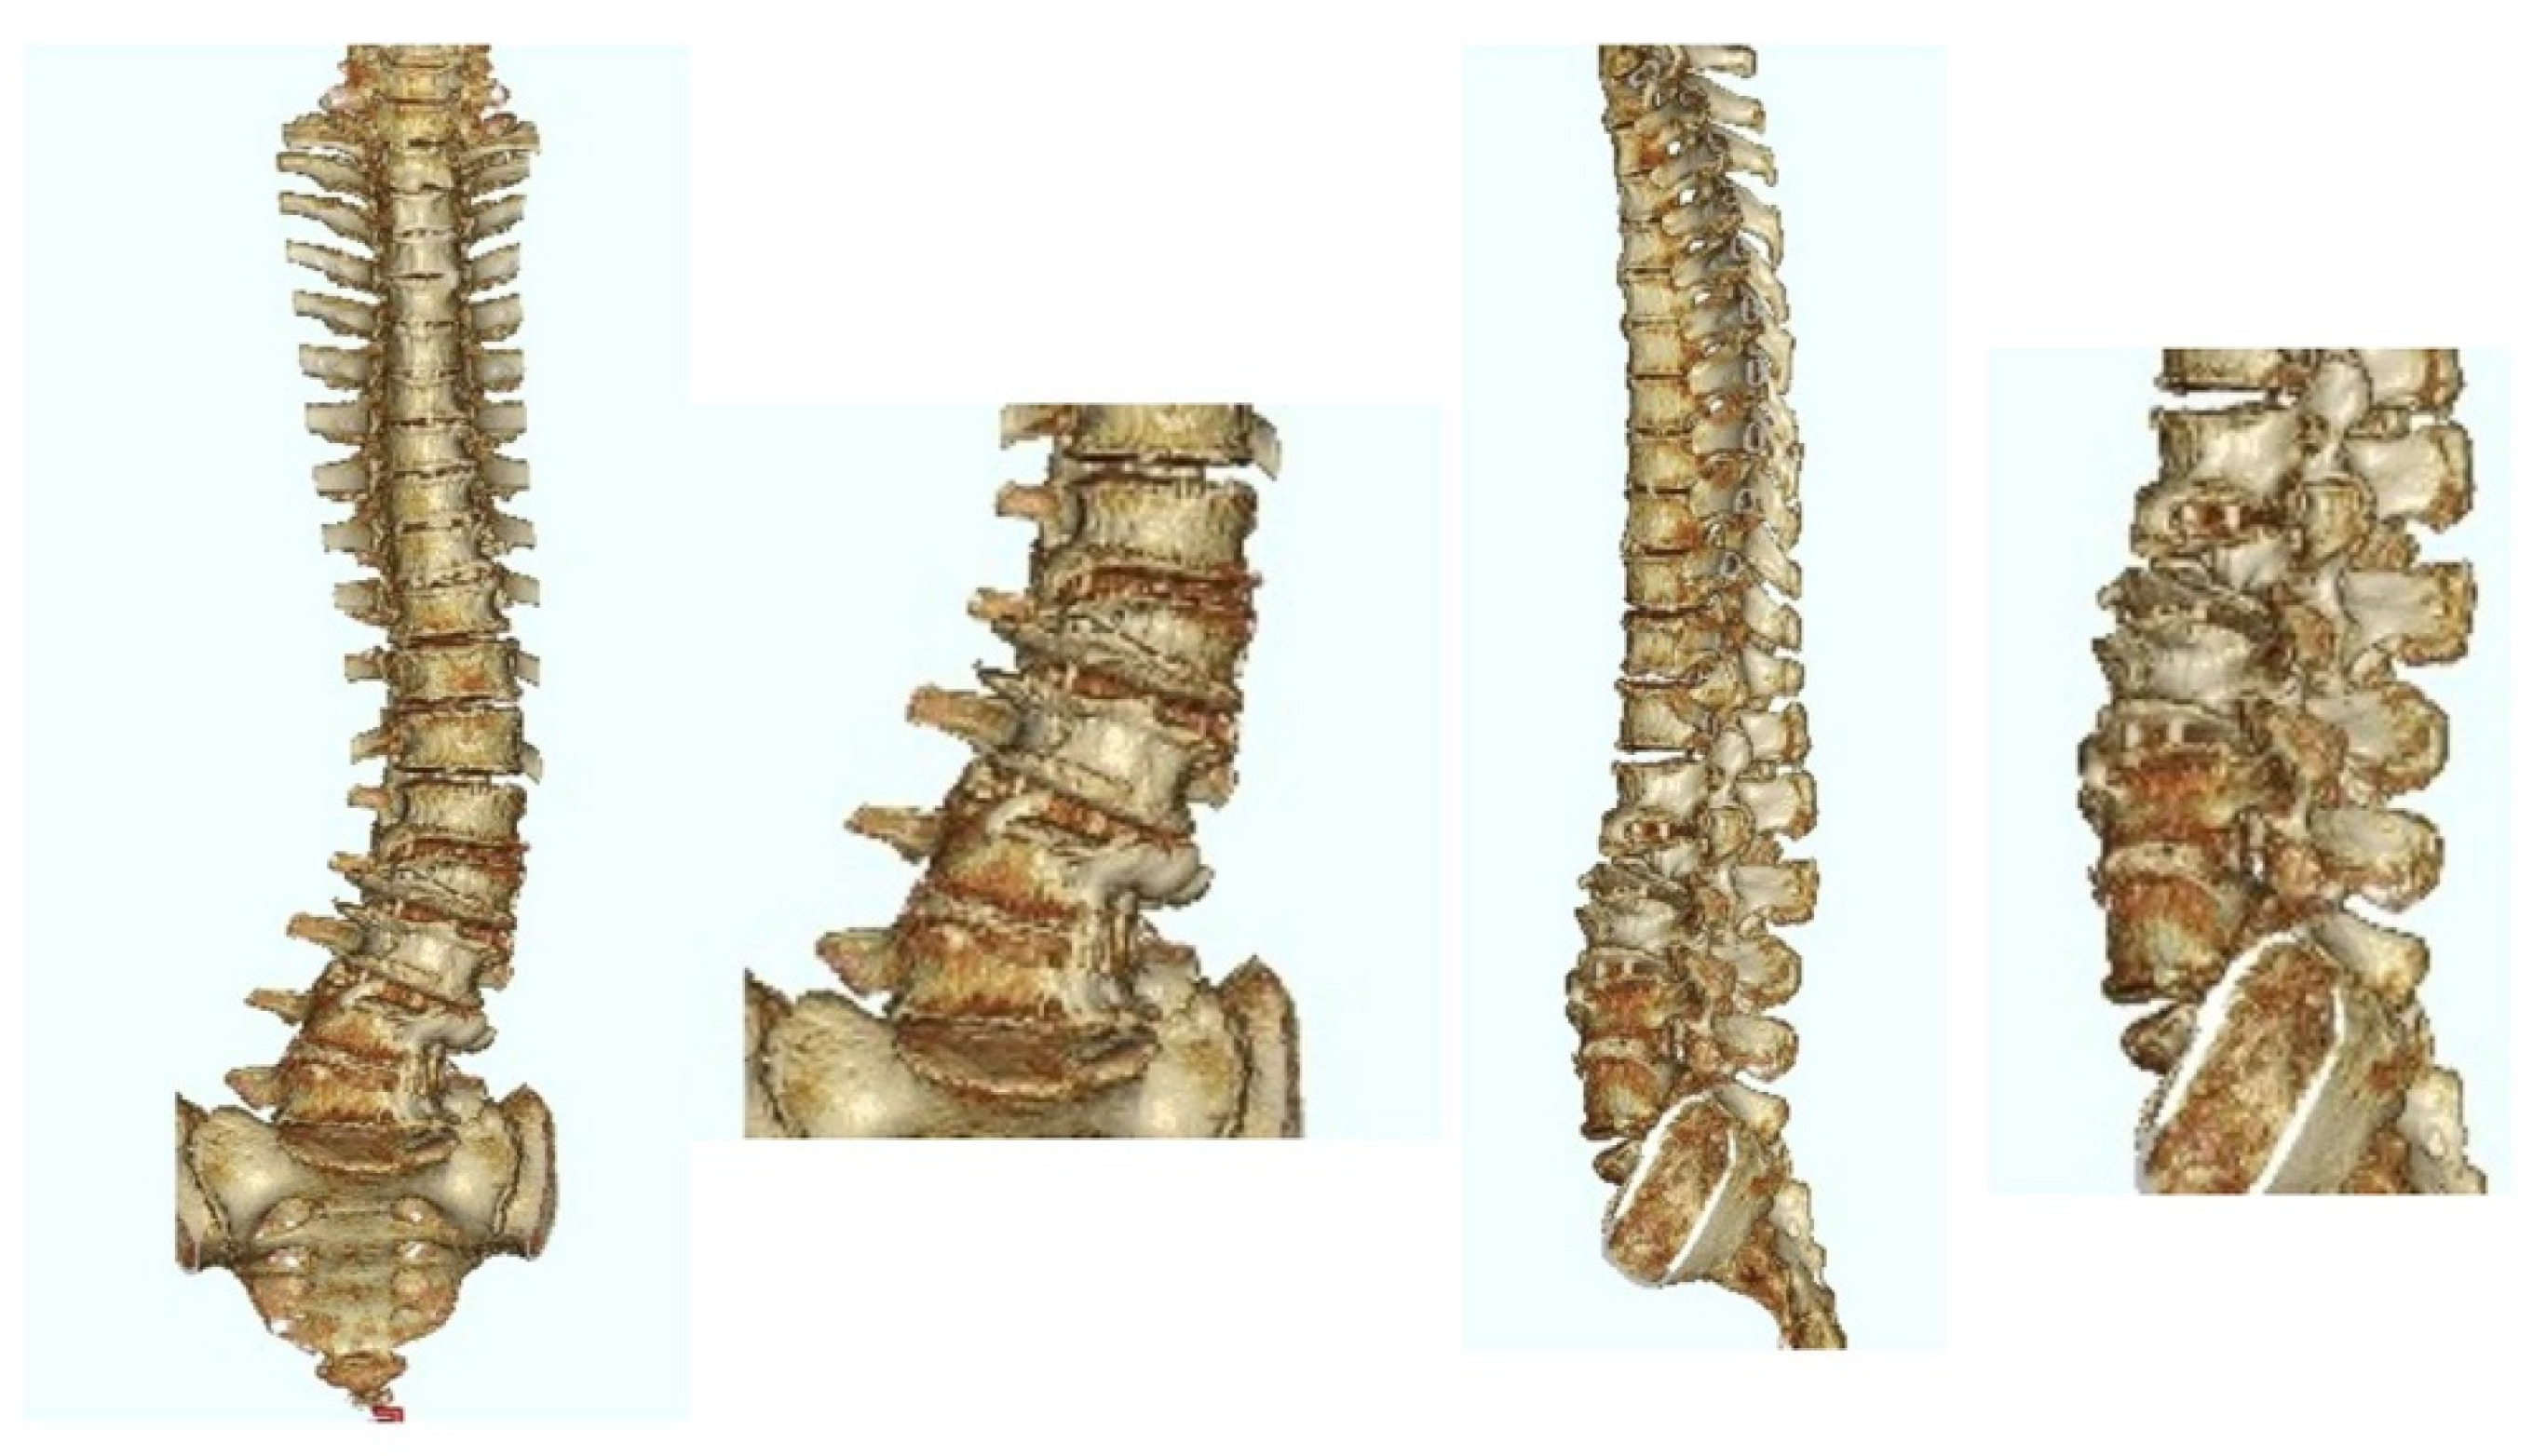

| Coronal L4 tilt (°) | Preop | 16.0 (6.8) | 28.7 (10.3) | 18.6 (9.1) | 0.001 * |

| Last | 7.3 (3.4) | 14.0 (5.1) | 8.7 (4.6) | 0.001 * | |

| p † | 0.002 * | 0.008 * | <0.001 * | ||

| Coronal L5 tilt (°) | Preop | 11.7 (7.7) | 17.4 (1.3) | 12.9 (7.3) | 0.002 * |

| Last | 6.7 (3.9) | 9.5 (2.4) | 7.3 (3.8) | 0.106 | |

| p † | <0.001 * | 0.001 * | <0.001 * | ||